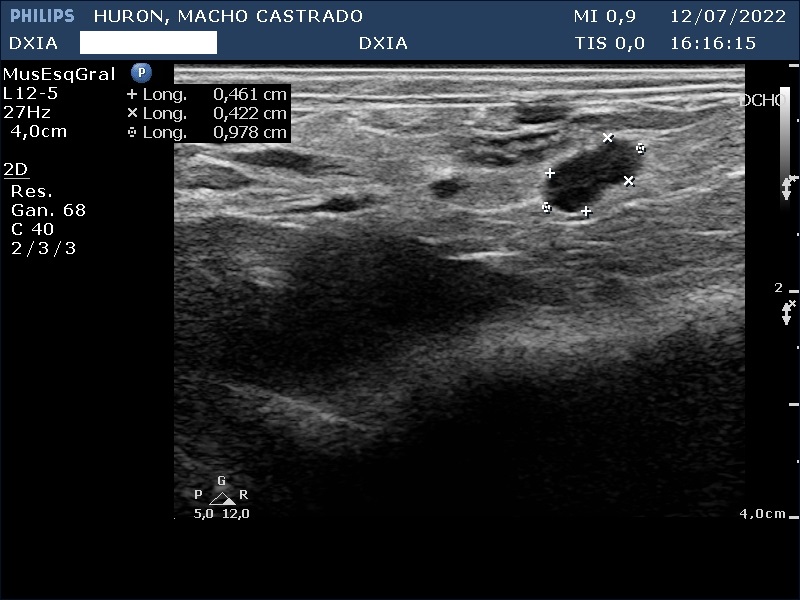

Hallazgos ecográficos